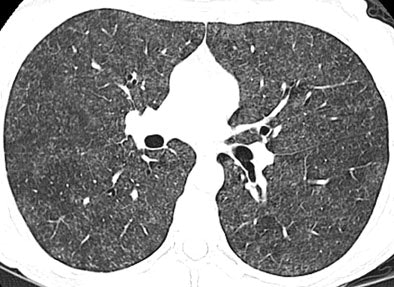

The results showed nodular opacities in 10 of the 12 (83%) of patients -- bilateral and symmetric in eight cases, and bilateral and asymmetric in two. The nodules involved more than 40% of the lungs in all 10 cases, according to the authors. Ground-glass attenuation (bilateral, symmetric in all cases) was seen in eight of the 12 (75%) cases, while the areas of ground-glass attenuation were diffuse in the cephalocaudal plane and randomly distributed in the transaxial plane.

| High-resolution CT image through lungs at level of bronchus intermedius in 54-year-old woman shows nodular areas of ground-glass attenuation with centrilobular distribution bilaterally. Image republished with permission of the American Roentgen Ray Society©, from AJR 2007; 188:1050-1053 by Thomas E. Hartmann, Eric Jensen, Henry D. Tazelaar, Viktor Hanak, and Jay H. Ryu. |

In the new pattern of pulmonary disease known as hot tub lung, "centrilobular nodules and areas of ground-glass attenuation are the most common findings, and typically have diffuse but patchy distribution throughout both lungs," Hartman and colleagues wrote. Expiratory images showed evidence of air trapping in all seven cases for which they were available, they added.